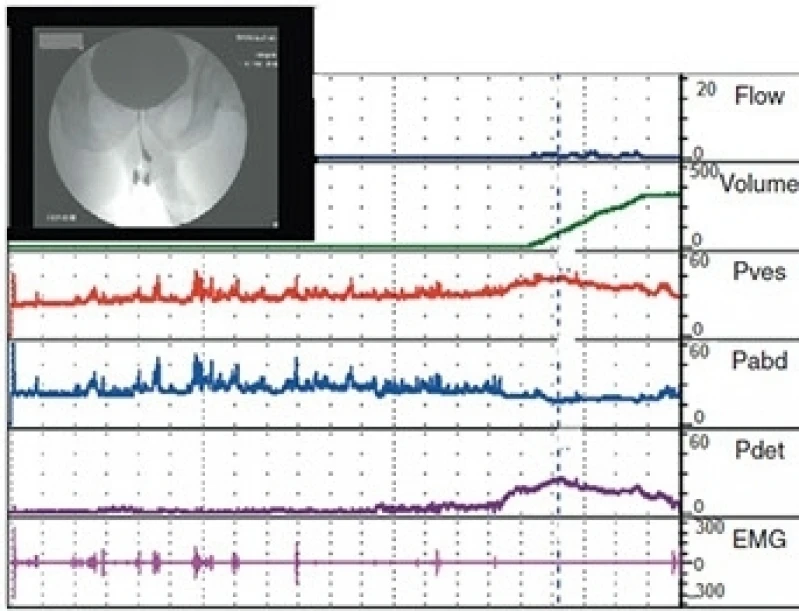

Pesquisando onde faz postectomia infantil Piqueri? Conheça nossos serviços, são opções variadas que oferecemos, como urologistas, vasectomia, estudo urodinâmico e cirurgias de fimose e tambem ultrassonografia de próstata. Contando com profissionais qualificados e experientes, o empreendimento entende a necessidade de cada cliente, buscando a sua satisfação e confiança.